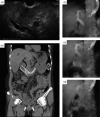

Background/purpose: This study aimed to evaluate the feasibility of endoscopic ultrasound (EUS)-guided antegrade covered stent placement with long duodenal extension (EASL) for malignant distal biliary obstruction (MDBO) with duodenal obstruction (DO) or surgically altered anatomy (SAA) after failed endoscopic retrograde cholangiopancreatography (ERCP).

Results: Twenty-five patients (DO, n = 18; SAA, n = 7) were included. The technical and clinical success rates were 96% and 84%, respectively. Reintervention occurred in two patients (8.3%). Adverse events occurred in six patients (24%; two cholangitis, 16%; four mild postprocedural pancreatitis [24% (n = 4/17) in patients with non-pancreatic cancers]). The median patency was 9.4 months, and the overall survival was 2.73 months. After IPTW adjustment, the median patency in the EASL (n = 25) and conventional EUS-BD (n = 29) were 10.1 and 6.5 months, respectively (P = .018).

Conclusions: EASL has acceptable clinical outcomes with a low reintervention rate but higher rate of postprocedural pancreatitis in patients with non-pancreatic cancers. Randomized trials comparing EASL and conventional EUS-BD for MDBO with pancreatic cancers and DO/SAA after failed ERCP are needed to validate our findings.